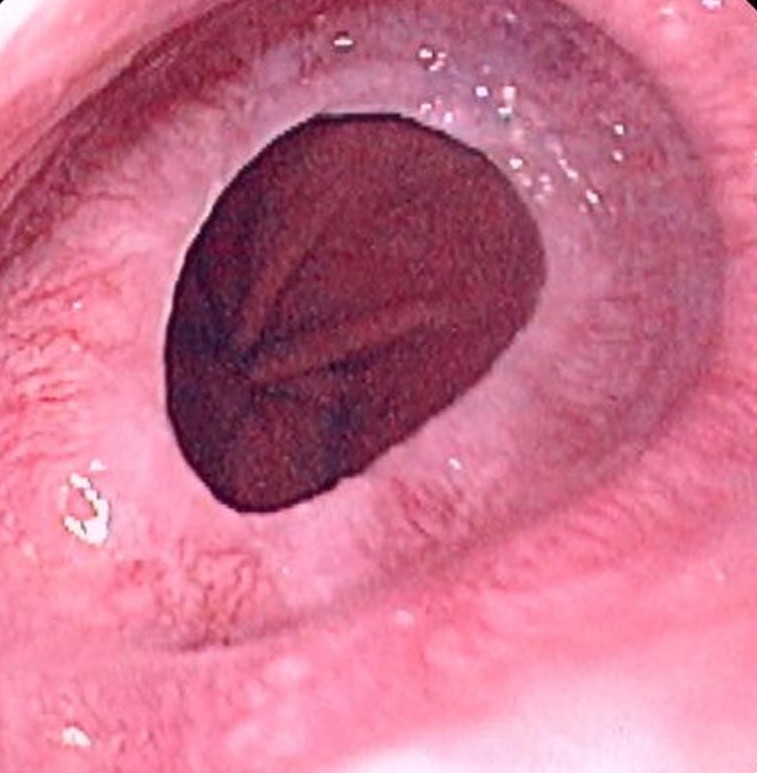

Es un reborde circunferencial delgado que se ubica en la mucosa del tercio inferior del esófago, en la unión escamocolumnar. Se presenta con frecuencia acompañado con hernia hiatal.

Se ha considerado que el anillo puede ser un doblez formado por un plegamiento interno de una mucosa que redunda por acortamiento del esófago; puede ser de origen congénito; o tratarse de una estenosis incipiente consecutiva a inflamación de la mucosa esofágica causada por reflujo crónico.

El anillo de Schatzki puede deberse a una lesión adquirida que causa estenosis por lesión química, originada por el alojamiento de medicamentos orales en la porción distal del esófago; o como consecuencia de reflujo que lesiona la mucosa esofágica inferior.